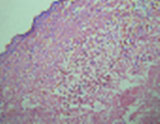

The excised specimen was sent for biopsy and histopathological examination revealed benign epidermoid vulval cyst (Fig. 3, 4). Post operative period was uneventful.